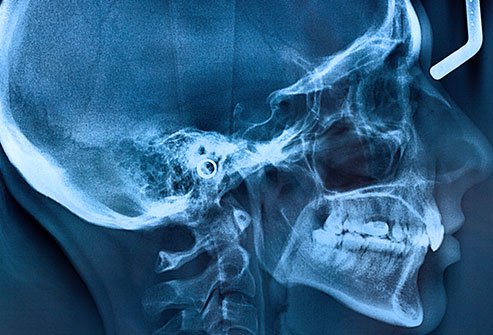

Broken Jaw (Mandible Fracture)

- Simple or closed: The fracture did not cause a break in the skin or mucosa or periodontal membrane. There is no connection between the jawbone and the environment.

- Compound or open: The jawbone is open to the environment.

- Comminuted: The jawbone region has bone splinters or crushed bone.

- Greenstick: One section of the jawbone is fractured while the other part is bent.

- Multiple: two or more distinct fractures of the jawbone

- Impacted: One section of bone is driven by force into another section.